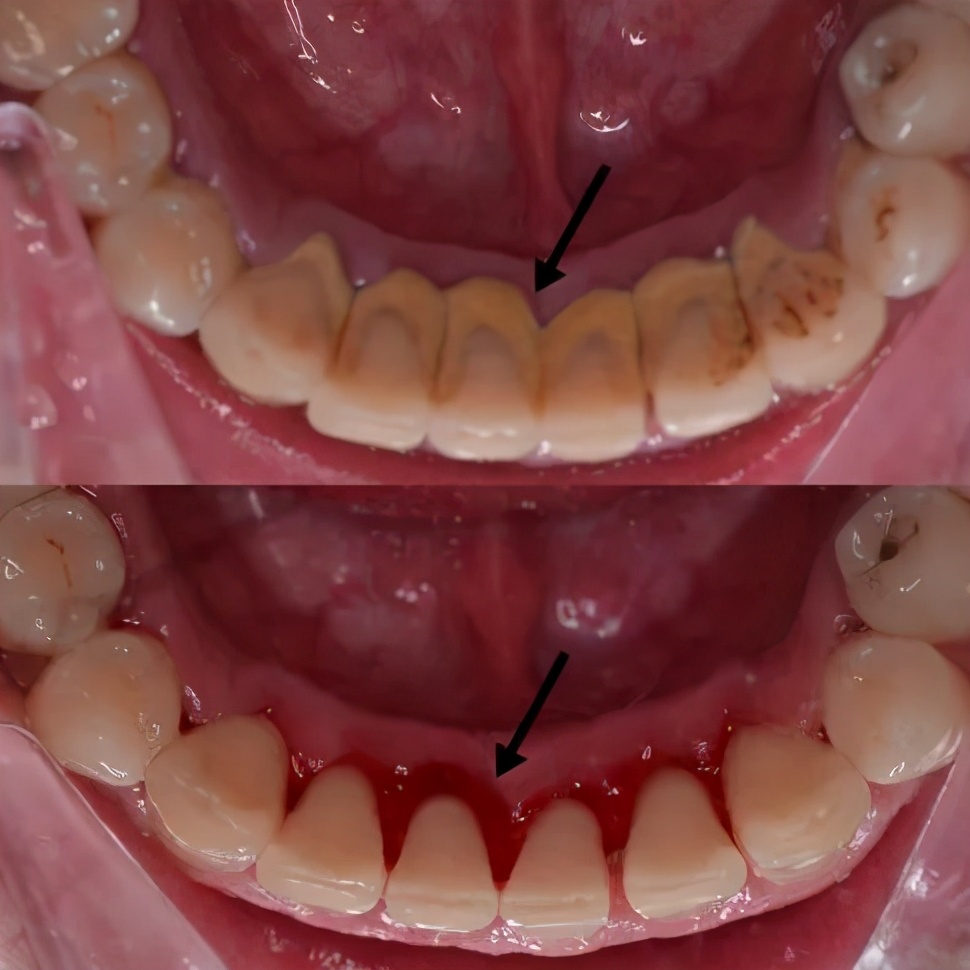

0280岁老人至少要有20颗能正常咀嚼、不松动的“好牙”[1]。预防掉牙记住12个字:早晚刷牙,饭后漱口,定期检查。03有人洗牙后感觉敏感不舒服,是牙结石清除后,牙龈重见天日(如下图),一时不适应导致的。

(作者供图)眼科